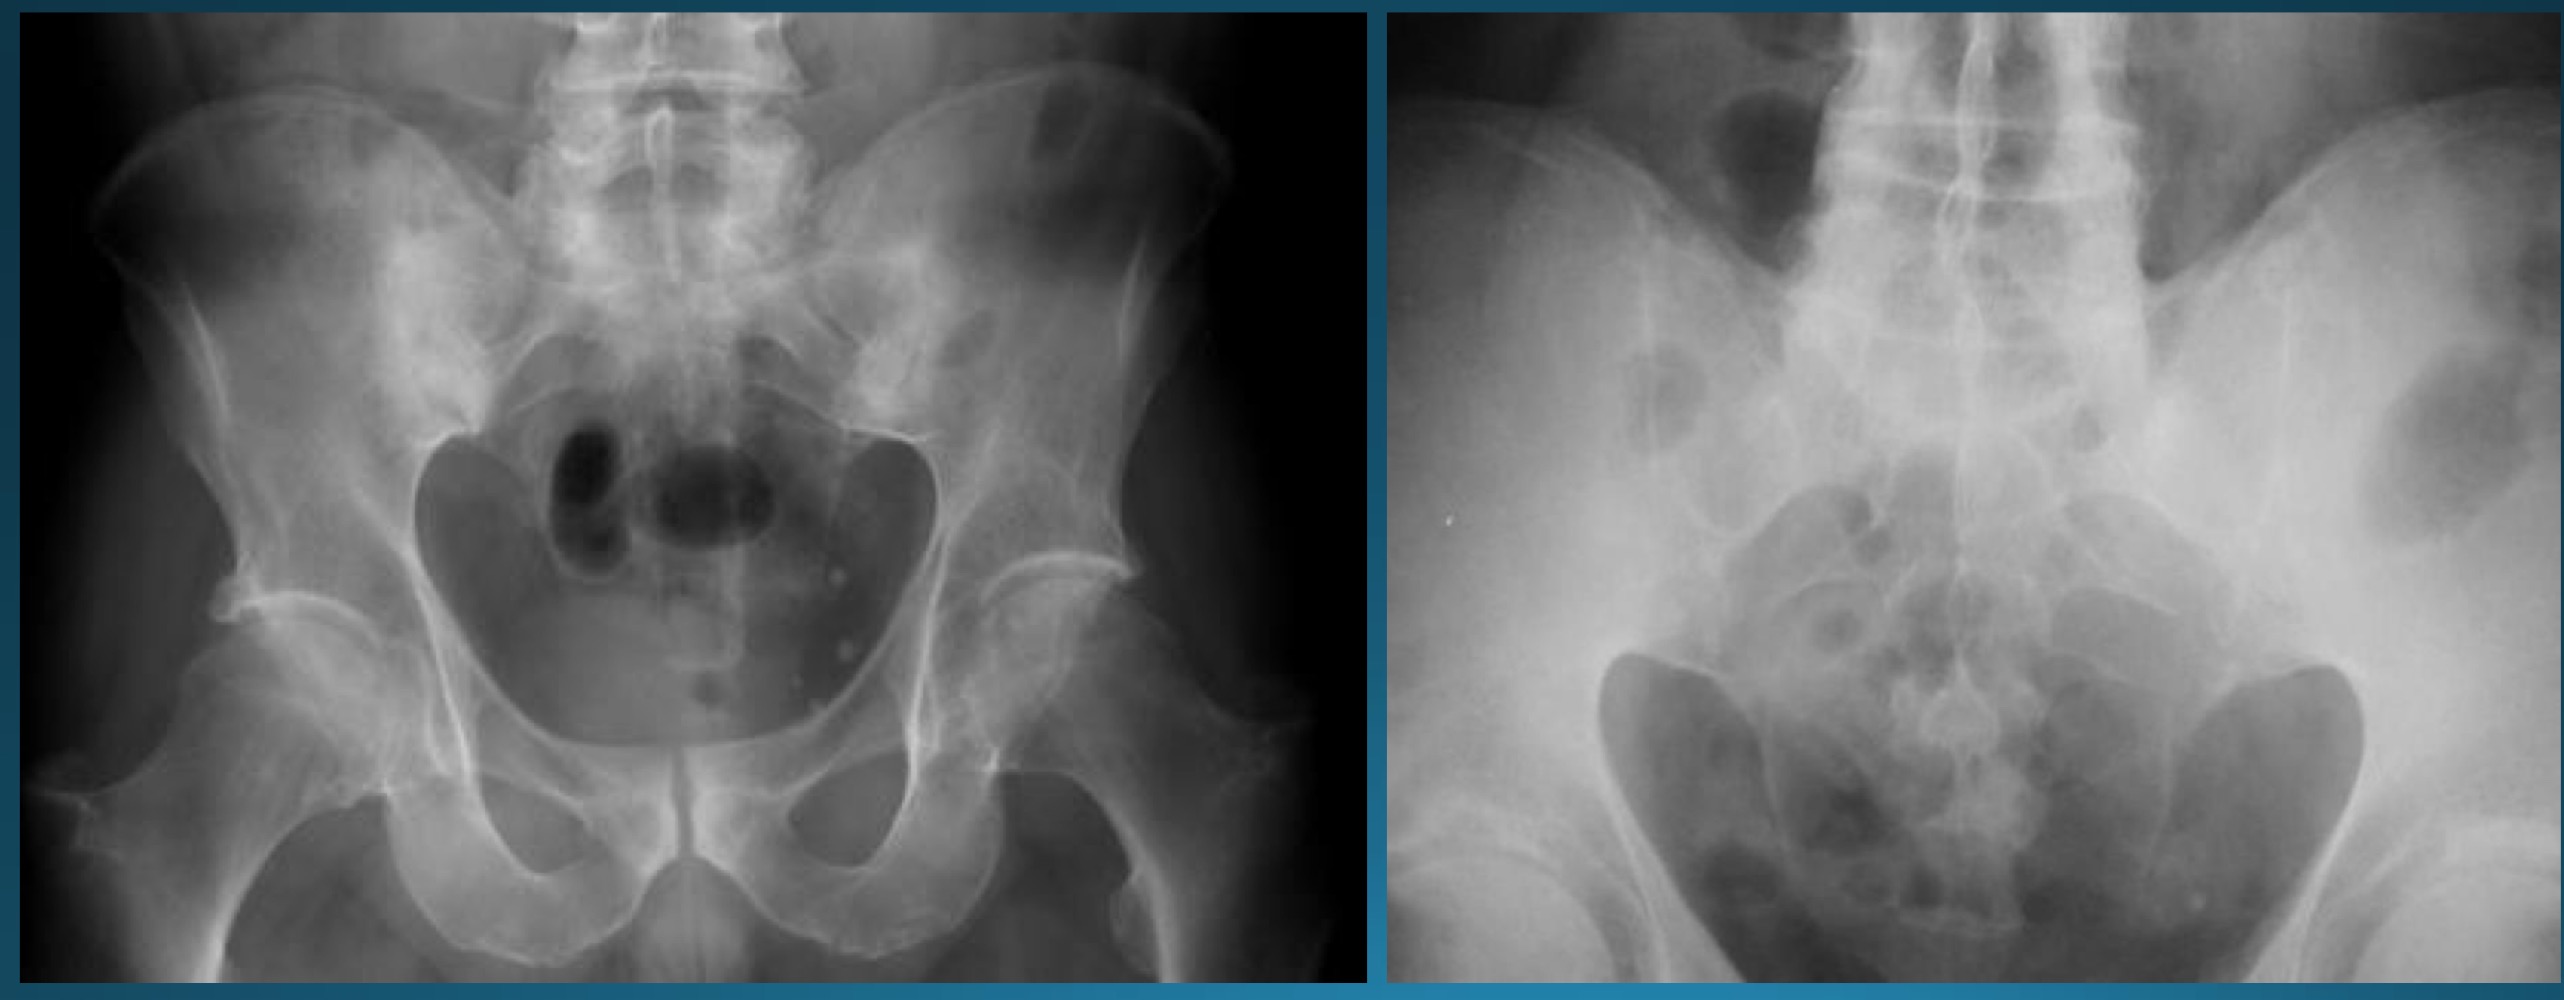

what are the signs seen in this image? what diagnosis would you make?

romanus lesion (erosion at corner of vertebral body )

shiny corner sign (sclerosis at angles of vertebral body romanus lesion)

AS

barrel shaped vertebra